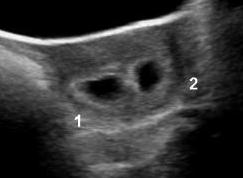

I went for an ultrasound on Monday June 6th at 6 weeks along. I still had little symptoms. I was just more tired than normal, had some food aversions and a bit of a bloated belly. They told me I was measuring 6w2d (they measure the crown to rump length of the baby). We couldn't really see too much as it was still early and, let's be honest, I am terrible at reading ultrasound photos.

Also the biggest news of all..there were two gestational sacs! We saw only one fetal pole, which was half hidden in the shadows, but they couldn't see anything in the second sac. So we had to wait two weeks for a follow up scan to see what may unfold. By then they said we should be able to see so much more. I was just glad to hear a bit of positive news. Even though my worries were not quenched in the least.

| 6w2d - Two sacs! |